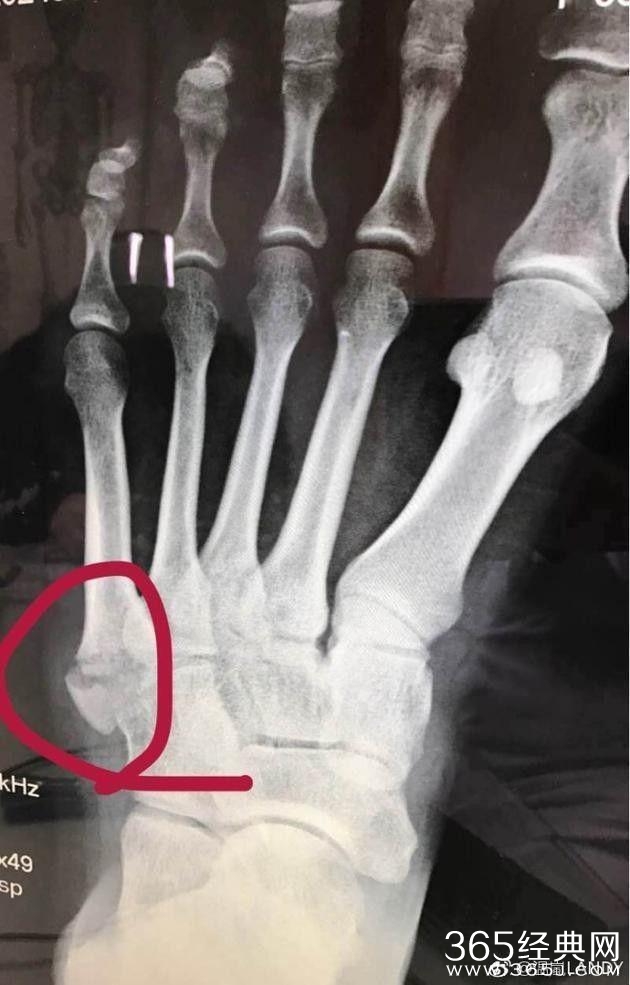

还po出来了骨折图给各人看,固然小编不是大夫,也看出骨头上貌似有一节错位了。并且看着温岚一边擦汗的行动我们也知道很惆怅的,看来当明星也不是那么好当的!